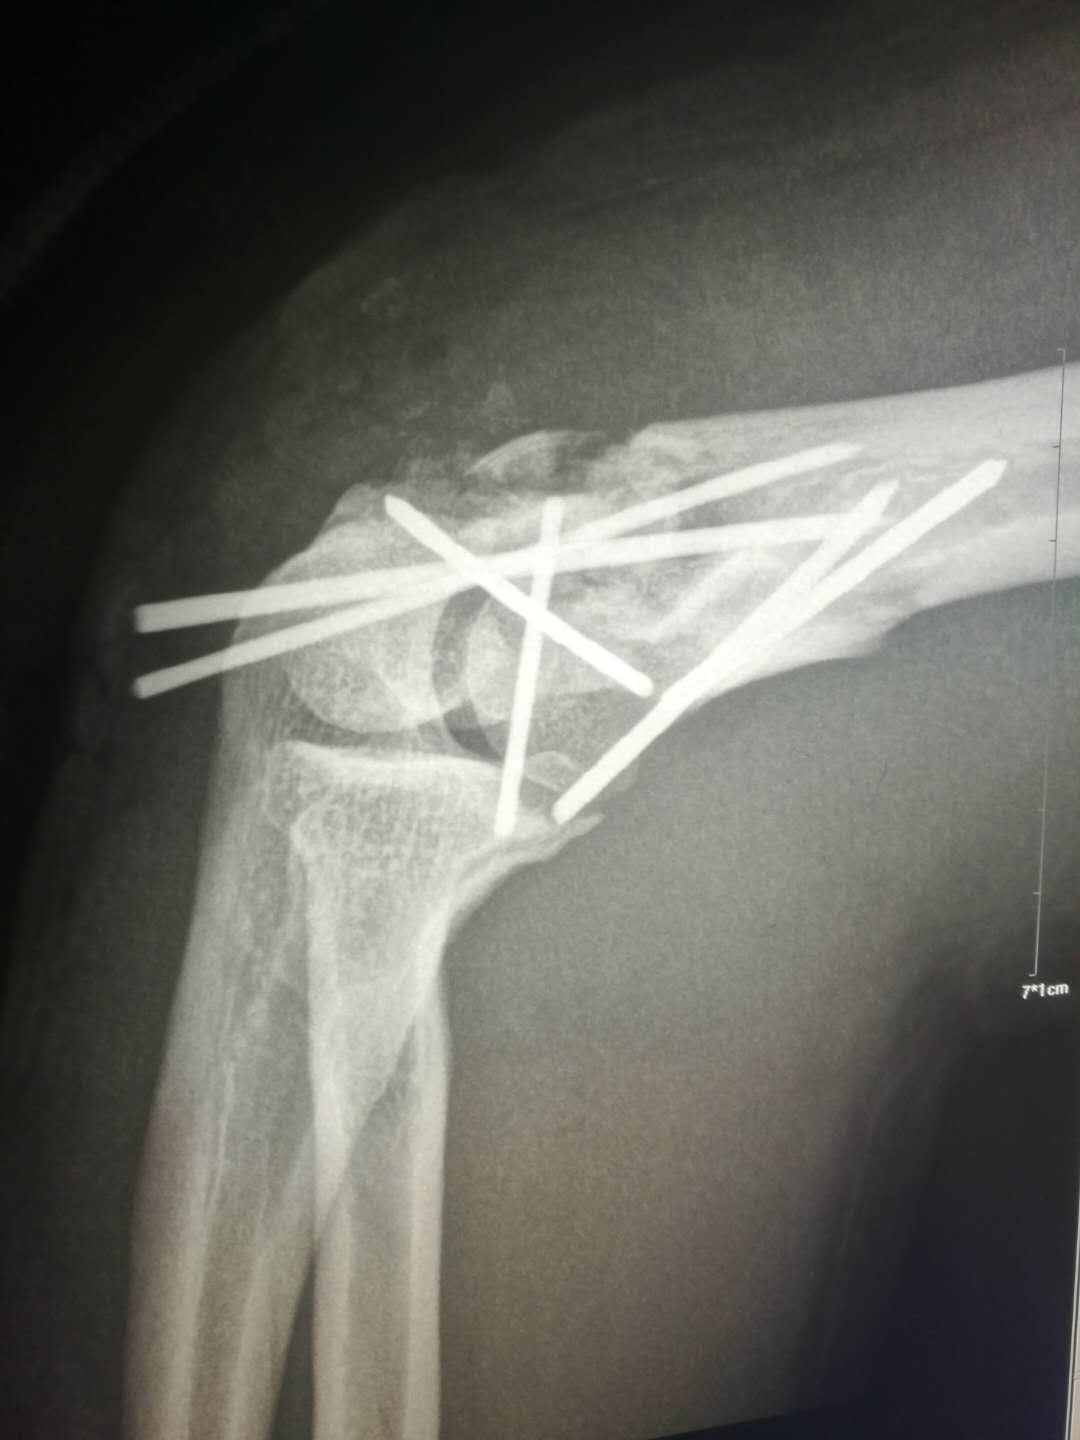

李某因不慎自约4米高处坠落,右肘部着地摔伤入院。 骨一科高长明副主任医师接诊病人后,为病人进行了仔细的查体,见其右肘部肿胀畸形,肘后有一伤口,骨头自伤口戳出,鲜血不断流淌,按压可触及明显的骨擦感,拍片见右肱骨髁粉碎性骨折,诊断为右肱骨髁开放性粉碎性骨折。开放性骨折需及早手术,但骨折粉碎,手术难度大,高医师当机立断,即刻实施手术。

术中见患者的肱骨髁已碎成20余块大小不等的骨块,均分离移位,高医师凭借丰富的手术经验,耐心地将碎骨块一块一块的拼接固定,历时3个小时,终于将骨块完好拼接,恢复了其原本的样貌。